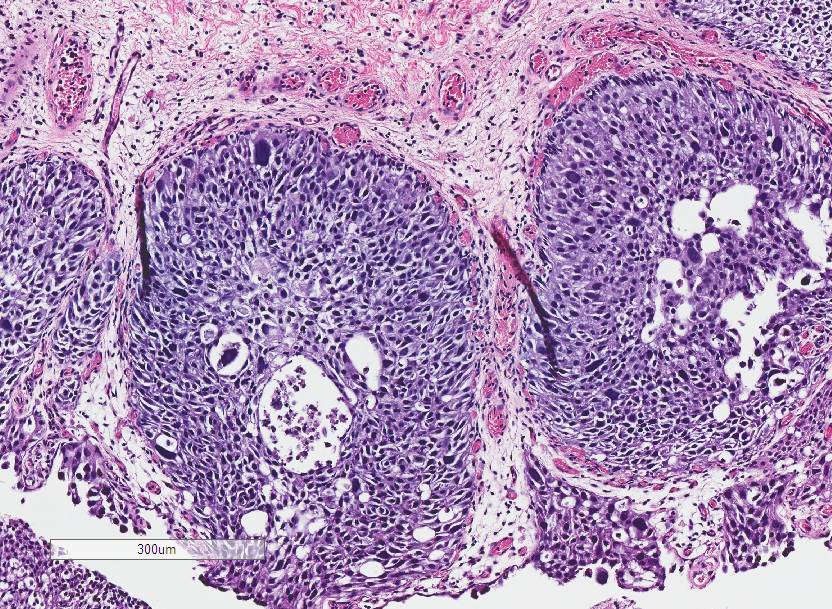

Bladder Papillary Lesions

Case ID: 640

Papilloma

PUNLMP

Low-grade papillary urothelial carcinoma (LG-PUC)

High-grade papillary urothelial carcinoma (HG-PUC)